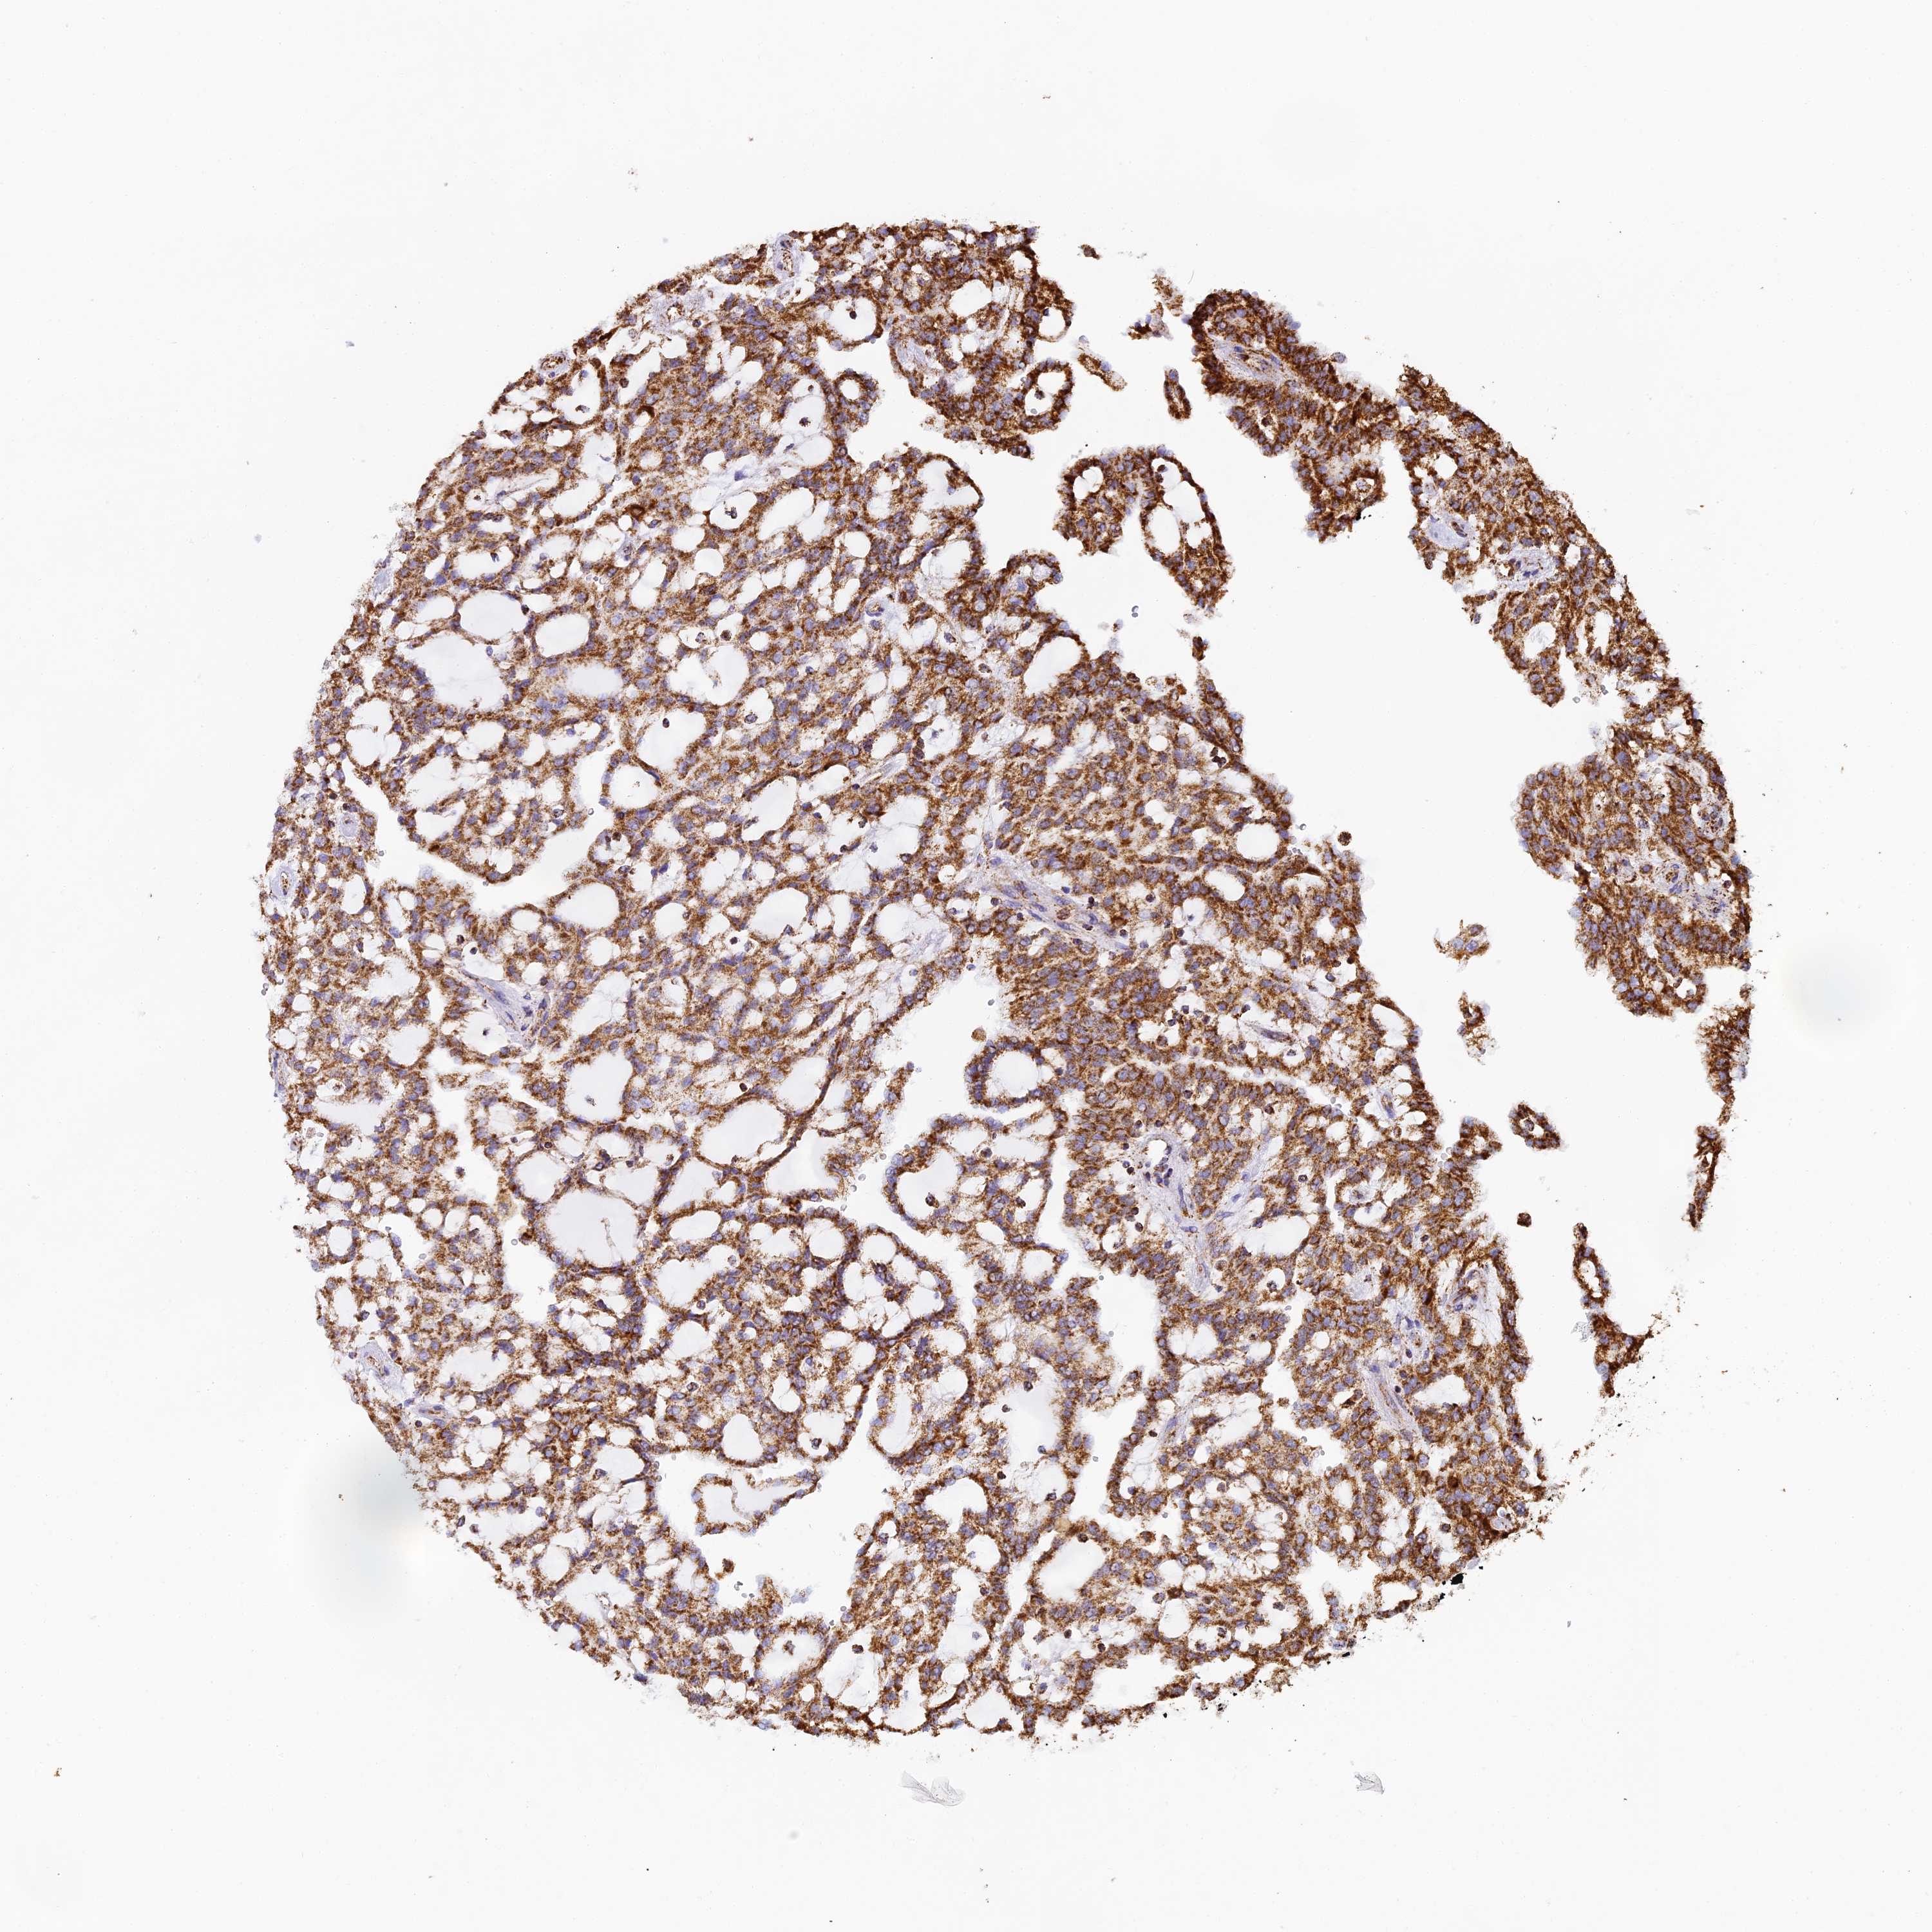

KIDNEY RENAL CLEAR CELL CARCINOMA (VALIDATION) - Interactive survival scatter ploti

The Survival Scatter plot shows the clinical status (i.e. dead or alive) for all individuals in the patient cohort, based on the same data that underlies the corresponding Kaplan-Meier plots. Patients that are alive at last time for follow-up are shown in blue and patients who have died during the study are shown in red.

The x-axis shows the expression levels (FPKM) of the investigated gene in the tumor tissue at the time of diagnosis. The y-axis shows the follow-up time after diagnosis (years). Both axes are complimented with kernel density curves demonstrating the data density over the axes. The top density plot shows the expression levels (FPKM) distribution among dead (red) and alive patients (blue). The right density plot shows the data density of the survived years of dead patients with high and low expression levels respectively, stratified using the cutoff indicated by the vertical dashed line through the Survival Scatter plot. This cutoff is automatically defined based on the FPKM cutoff that minimizes the p-score. The cutoff can be changed by dragging the vertical line or by entering a cutoff value in the square labeled "Current cut-off".

Under the Survival Scatter plot the p-score landscape (black curve; left axis) is shown together with dead median separation (red curve; right axis). Dead median separation is the difference in median mRNA expression between patients who have died with high and low expression, respectively. It is calculated as follows: median FPKM expression of dead patients with high expression - median FPKM expression of dead patients with low expression. This is intended to aid the user in visually exploring custom cutoffs and the associated p-scores and dead median separation.

Individual patient data is displayed and can be filtered by clicking on one or more of the category buttons on the top of the page. Categories describing expression level and patient information include: high, low, alive, dead, female, male and tumor stages. The scale of the x-axis can be toggled between linear and log-scale by clicking on the "x log" button. Mouse-over function shows TCGA ID, patient information and mRNA expression (FPKM) for each patient.

& Survival analysisi

Kaplan-Meier plots summarize results from analysis of correlation between mRNA expression level and patient survival. Patients were divided based on level of expression into one of the two groups "low" (under cut off) or "high" (over cut off). X-axis shows time for survival (years) and y-axis shows the probability of survival, where 1.0 corresponds to 100 percent.

STK17A is not prognostic in Kidney Renal Clear Cell Carcinoma (validation)

Best expression cut offi

Based on the FPKM value of each gene, patients were classified into two groups and association between prognosis (survival) and gene expression (FPKM) was examined. The best expression cut-off refers the FPKM value that yields maximal difference with regard to survival between the two groups at the lowest log-rank P-value. Best expression cut-off was selected based on survival analysis .

When clicking on this number, the vertical dashed line indicating cut-off, the interactive survival plot, and the Kaplan-Meier curve will be adjusted to show results based on the best expression cut-off.

: 5.02

P scorei

Log-rank P value for Kaplan-Meier plot showing results from analysis of correlation between mRNA expression level and patient survival.

N/A

TCGA RNA samplesi

RNA-seq data is reported as average FPKM (number Fragments Per Kilobase of exon per Million reads), generated by the The Cancer Genome Atlas (TCGA) .

Normal distribution across the dataset is visualized with box plots, shown as median and 25th and 75th percentiles. Points are displayed as outliers if they are above or below 1.5 times the interquartile range. FPKM values of the individual samples are presented next to the box plot.

Average pTPM 7.0

Number of samples 100